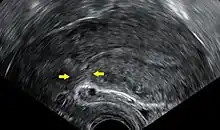

Transvaginal ultrasonography of a uterus years after a caesarean section, showing the characteristic scar formation in its anterior part